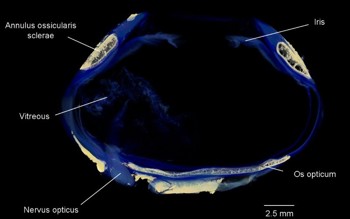

Fig 3. Micro-CT of a king penguin, Aptenodytes patagonicus, eye – note the aspheric

shape of the eye and the bony elements within (beige), the annulus ossicularis sclerae

and the os opticum

In both humans and birds, the sclera is relatively avascular and predominantly collagenous, however, birds have retained a cartilaginous cup around the posterior aspect of the globe (Fig 2), possibly to prevent deformation during accommodation. Birds also possess a ring of overlapping small plates in the anterior sclera. Proposed functions include maintenance of the aspheric shape of the globe, protection, resistance to compression or deformation during extensive accommodation in diving birds and a point of attachment for both intrinsic and extrinsic ocular musculature. Another common bone is the os opticum, around the disc. Not present in all birds, its function is unknown7.